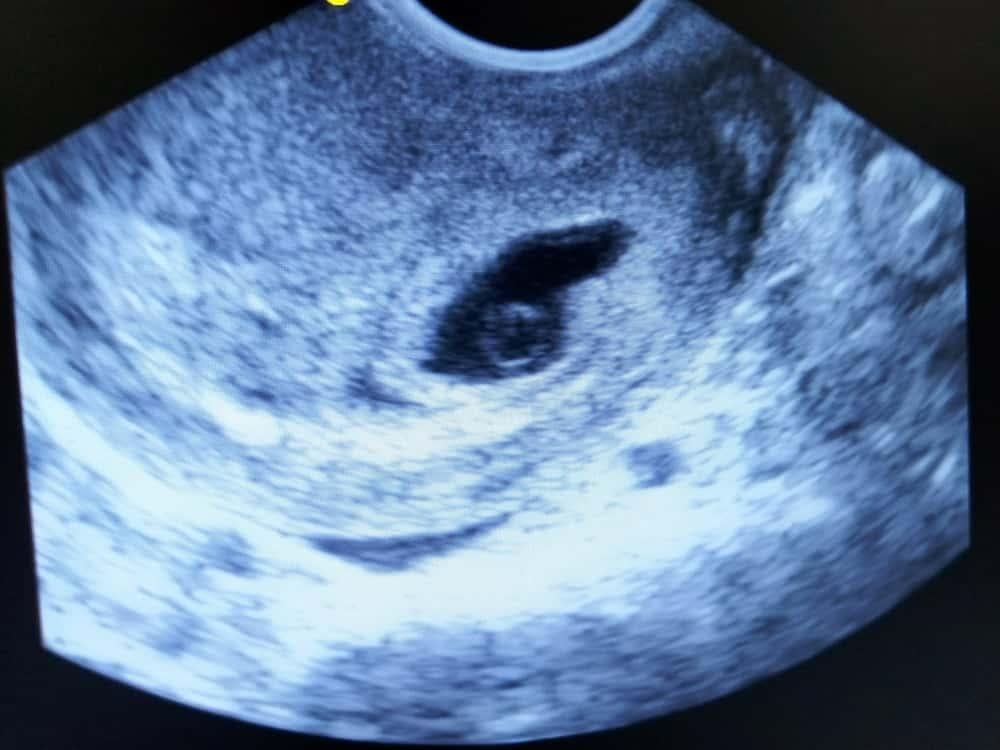

2. Giải đáp thắc mắc: Túi thai 6mm là mấy tuần, có phôi thai chưa?

Túi thai 6mm là mấy tuần? Như vậy, nếu kết quả siêu âm cho thấy túi thai 6mm nghĩa là bạn đã có thai được khoảng 4-5 tuần.

Trở lại với thắc mắc túi thai 6mm có phôi thai chưa? Câu trả lời là “chưa”. Theo các chuyên gia sản khoa, ở tuần thứ 6-7 của thai kỳ, phôi thai mới bắt đầu hình thành và phát triển bên trong túi thai. Phôi thai lúc này chỉ là một khối nhỏ, có đường kính khoảng 0,5mm.